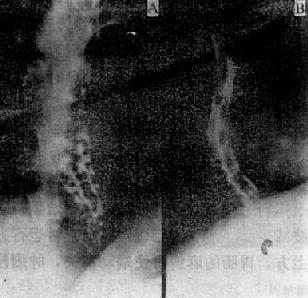

早期食管静脉曲张发生于食管下段,表现为粘膜皱襞稍增宽或略为迂曲,有时因皱臂显示不连续而如虚线状,管壁边缘也稍不整齐。典型表现为食管中下段的粘膜皱襞明显增宽、迂曲,呈蚯蚓状或串珠状充盈缺损,管壁边缘呈锯齿状(图4-2-8)。病变加重。上述表现则更为明显,食管张力降低,管腔扩张,蠕动减弱,钡剂排空延迟,病变也逐渐向上发展。本病的食管壁柔软而伸缩自如,是与食管癌的重要鉴别点。

轻度中度

图4-2-8 食管静脉曲张

食管粘膜皱增粗、扭曲,呈串珠状